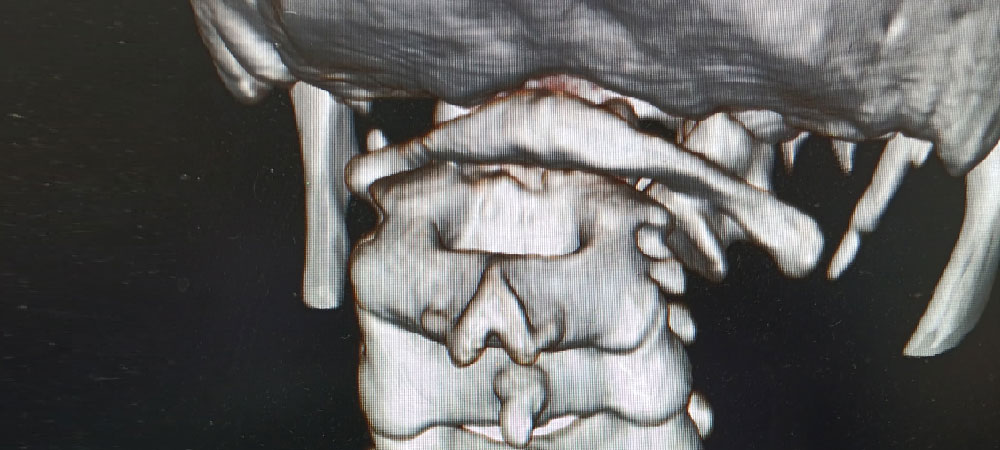

Leading spine surgeon in North Bengal & Siliguri, specializing in minimally invasive techniques for effective, faster recovery. With easier access to advanced dental technologies, you can now get personalized care plans for spinal conditions, chronic back pain, and disc issues.

Expert in diagnosing and treating complex spinal conditions with the latest surgical techniques.

Dr. Mayukh Guha, an experienced spine surgeon in Siliguri, offers expert diagnosis and advanced minimally invasive treatments. He is committed to delivering personalized care for various spinal conditions.

Using the latest spine surgery tools and techniques, Dr. Guha ensures precise treatment tailored to each patient's unique needs. At the best spine clinic in Siliguri, North Bengal, he offers minimally invasive procedures that promote faster recovery and lasting relief.